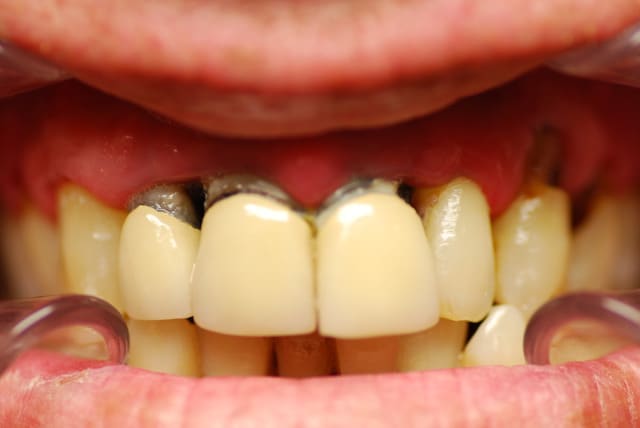

Bonjour à tous,

je fais remonter le post, avec quelques photos faisant suite à la séance "dépose des pf et mise en place du bridge provisoire. Aucun tenon provisoire mais le bridge tient très bien.

L'état paro s'est trés nettement amélioré, avec le protocole d'assainissement( Listérine verte+ Bicarbonate -eau oxygénée).

Impossible cependant de déposer le tenon de la 21, au risque de fracturer la racine selon moi. Ce sera donc chir apicale pour cette dent.

Ps; désolé pour la salive sur les photos, j'étais légèrement speed pendant cette séance:)